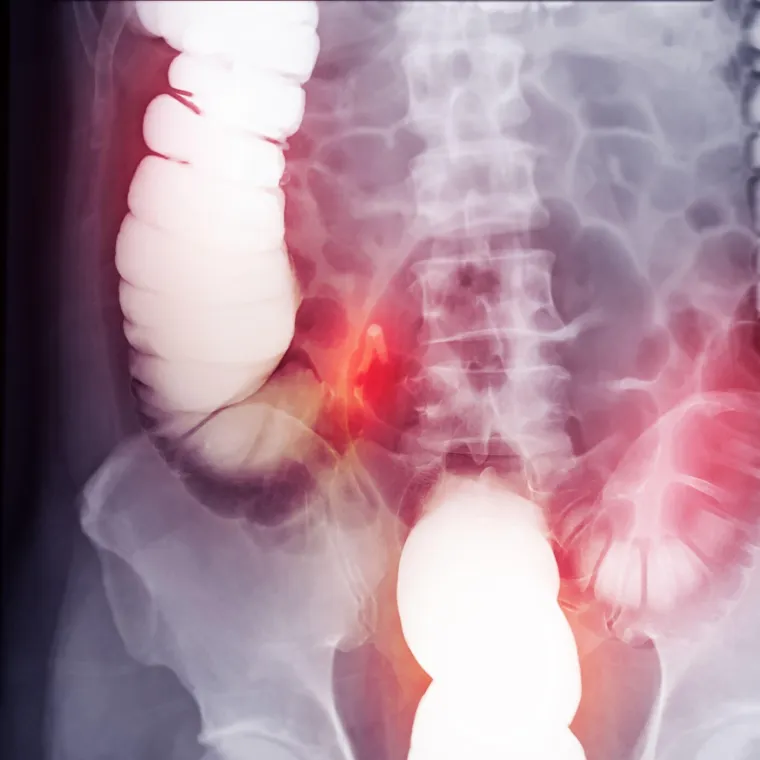

Raste broj slučajeva zaboravljenog raka kod mladih: Simptome je lako zanemariti

Rak se može razviti u slijepom crijevu, obično bez ikakvih znakova upozorenja, a raste broj oboljelih

Slijepo crijevo je mala vrećica u obliku prsta pričvršćena za debelo crijevo. Njegova svrha u tijelu još se uvijek raspravlja, ali najpoznatiji je po tome što uzrokuje bolnu upalu slijepog crijeva, koja često zahtijeva hitnu operaciju. Manje je poznato da se rak može razviti u slijepom crijevu, obično bez ikakvih znakova upozorenja.

Ono što rak slijepog crijeva čini posebno izazovnim jest koliko ga je teško otkriti. Za razliku od raka debelog crijeva, koji se ponekad može rano otkriti probirnim kolonoskopijama, rak slijepog crijeva obično prolazi ispod radara.